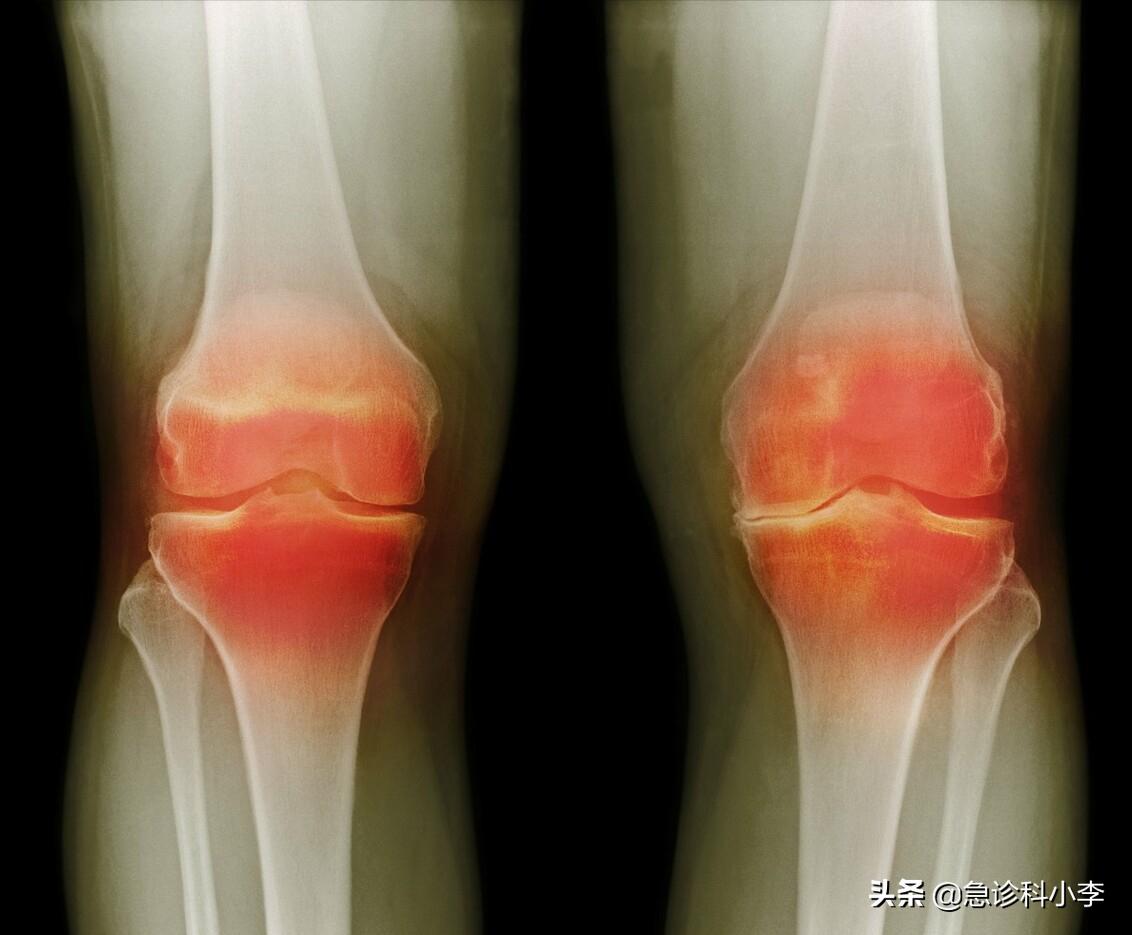

第三种:类风湿性关节炎

类风湿性关节炎是一种由 体内自身免疫性疾病引起的慢性疾病 ,当免疫系统错误地攻击人体自身组织时就会发生这种疾病。

这种疾病会引起炎症(发红、肿胀),导致关节疼痛、僵硬和肿胀,主要是手、背、脚和膝盖的关节。

类风湿性关节炎不仅会破坏身体的关节,还会损害整个身体系统,包括皮肤、眼睛、肺、心脏和血管。

迄今为止,还没有治愈这种疾病的方法 。而治疗的主要目标是缓解疼痛、控制症状、提高生活质量和预防未来出现危险的并发症。